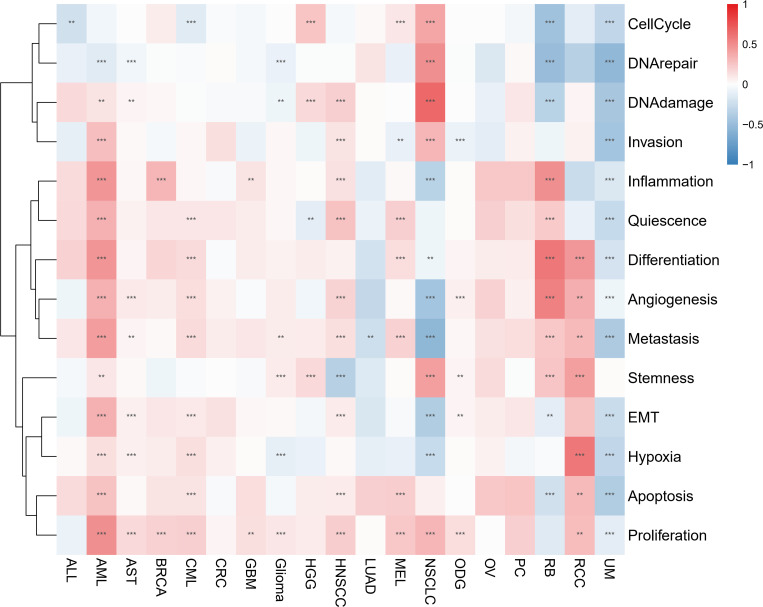

Single-cell functional analysis of IFN-γ

Through examining the CancerSEA dataset, we compared the IFN-γ score to 14 different functional statuses of cancers. In AML, the IFN-γ score was positively correlated with inflammation, invasion, quiescence, differentiation, angiogenesis, metastasis, EMT, and other functions, but negatively correlated with 13 functions in UM. In 11 types of tumors, there was a favorable correlation between the IFN-γ score and proliferation (f8). Combined with the information on drug responsiveness from The Cancer Therapeutics Response Portal database and information on gene expression profiles of tumor cell lines, we found that twenty of thirty drugs’ sensitivities were shown to be positively linked to STAT1. IFN-γ-related genes may serve as a target for research into these medications and targeted therapy for cancer (Supplementary Table 2).